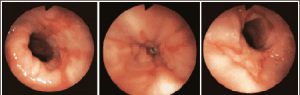

- Для диагностики используется эндоскопия во время эзофагогастроскопии на 7-й и 21-й день.

При ожоге пищевода существуют три степени тяжести поражения, которые зависят от времени воздействия агрессора, его типа, происхождения и концентрации. При сложном травмировании признаки поражения более выражены. Существуют три степени ожоговой тяжести:

Легкая степень. В этом случае поражается верхний слой пищевода, что проявляется покраснением, отечностью и повышенной ранимостью стенок. Симптомы обычно исчезают через 2 недели.

Средняя степень. В этом случае поражается слизистая и мышечная ткань пищевода, сопровождающаяся сильным отеком, изъязвлением и стенозом. С течением времени раны покрываются фибрином. При отсутствии осложнений пищевод заживает за 30 дней.

Тяжелая степень. В этом случае поражается вся глубина слизистой, а также близлежащая клетчатка и органы, сопровождающиеся шоком и интоксикацией. Образуются грубые рубцы, развивается стеноз с укорочением пищевода. При правильной и своевременной первой помощи заживление может занять от 90 дней до 2 лет.